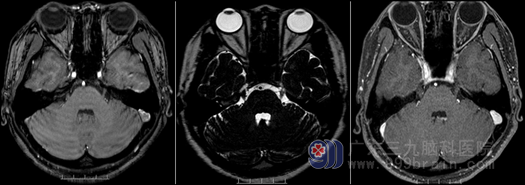

王女士10年前无明显诱因出现了左侧颜面部发作性疼痛,呈触电样,以左侧额颞部、眼眶周围为主,每两年发作性疼痛一个月左右,发作时无明显诱因,发作时间短至数分钟,长则一个小时左右,痛后可自行缓解,当时未进行进一步检查及治疗,近一个月来王女士感到左侧颜面部疼痛较前明显加重,发作频率也比之前增加了,无明显诱因头面剧痛,甚至伴有恶心呕吐等不适症状,曾到当地医院就诊,口服“卡马西平”,但服药后又明显头晕,为求进一步治疗,辗转来到广东三九脑科医院就诊,MR显示:“左侧三叉神经颅内段上方分别示一细小血管水平骑跨伴行”,门诊以“三叉神经痛”收住神经外十科。